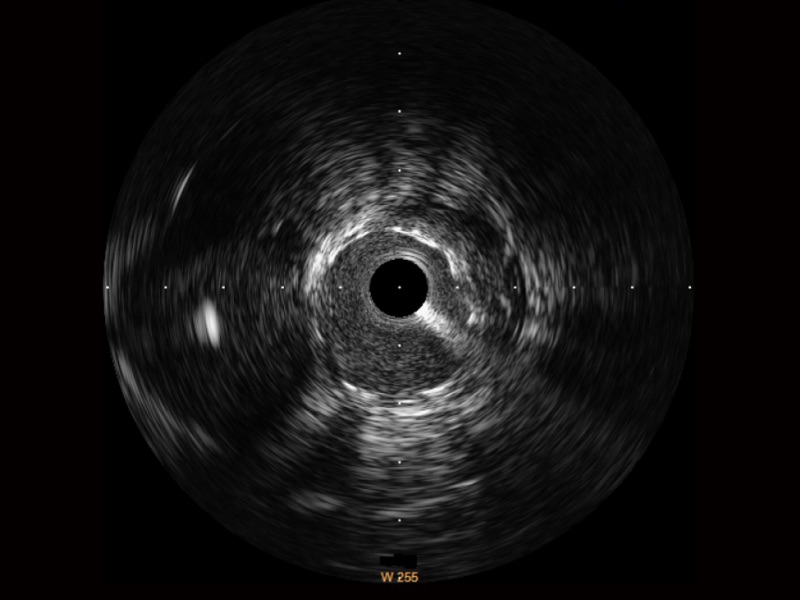

传统IVUS图像

对比传统IVUS导管成像,竞技宝(JJB)官方网站宽频IVUS图像的近场支架梁显影更细腻,远场中膜外血管仍清晰可辨,兼顾远中近,兼顾分辨力与穿透深度